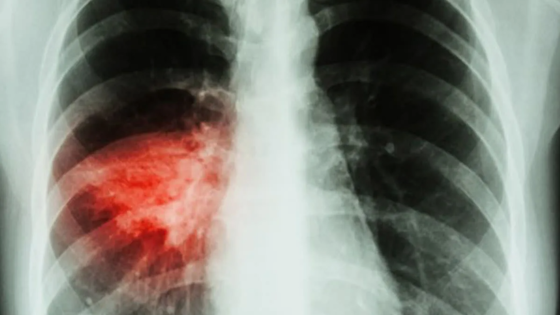

В Тюменской области зафиксирован резкий рост внебольничных пневмоний

Последние две недели в Тюменской области наблюдается тревожная тенденция - резкий рост случаев внебольничной пневмонии. По данным областного управления Роспотребнадзора, этот показатель достиг 63 на 100 тыс. населения. Ситуация осложняется сезонным ростом заболеваемости ОРВИ и коронавирусом, что, по мнению специалистов, связано с началом учебного года и формированием детских и трудовых коллективов.